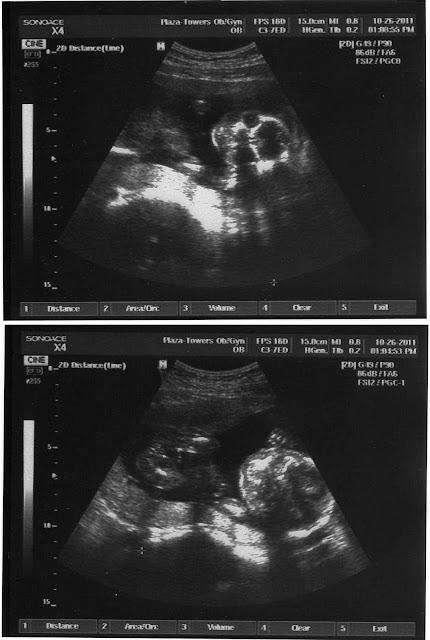

WEEK 20

Ok.  This ultrasound is even harder to decipher than Week 12's ultrasound.

Here are the captions

The baby is about 6.5 inches here from head to butt.   And roughly 10 inches from head to toes.